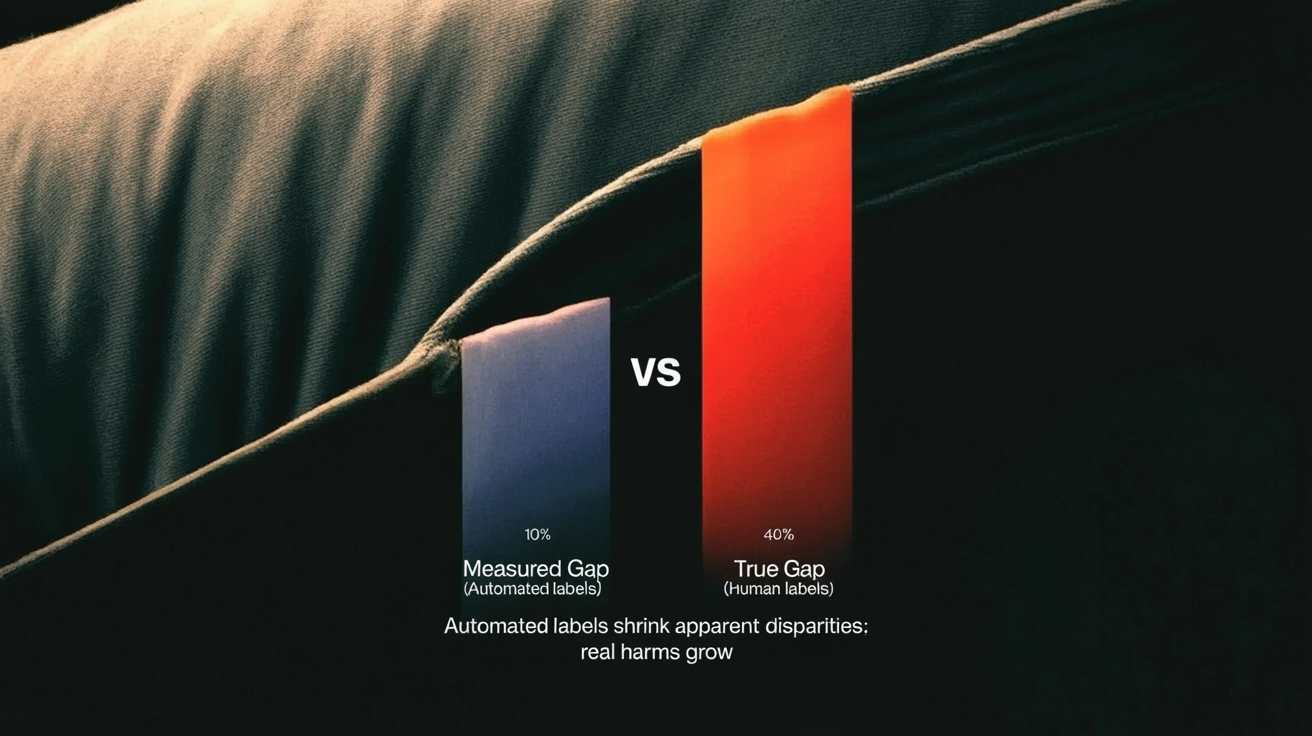

- Automated labeling bias turns benchmarks into a biased ruler: models agree with bad labels and look “fair” while failing real patients.

- In breast MRI, younger patients don’t just have noisier labels, they have qualitatively harder tumors, so training on automated labels can amplify age bias by ~40%.

The MAMA‑MIA audit finds something nastier: when you train segmentation models directly on the biased automated labels, age disparities grow, by on the order of 40% in their experiments, compared to training on cleaner human annotations.

The benchmark reports narrow gaps or none at all. Underneath, the model’s actual performance divergence has widened.

- Small fairness gaps in benchmark tables aren’t evidence of safety; they might be evidence of shared delusion between model and labels.

It also changes what “scaling up” means. Automated annotation has been sold as a neutral tradeoff: a little noise in exchange for a lot more data. The MAMA‑MIA audits say: not neutral. When the noise is structured by age, ethnicity, site, by who is already underserved, more data can mean more damage, and better‑looking numbers.